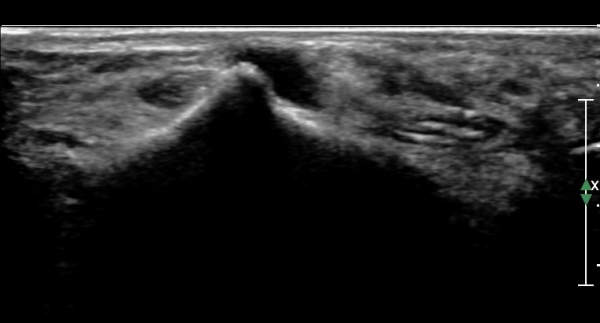

ÃÊÀ½ÆÄ°Ë»ç : ¹ß¸ñ °üÀý Á¾´Ü¸é°Ë»ç¿¡¼­ ¹ß¸ñ °Å°ñ ¿¬°ñÀÌ ¾ã¾îÁ®(thinning) º¸ÀδÙ(»çÁø 1).